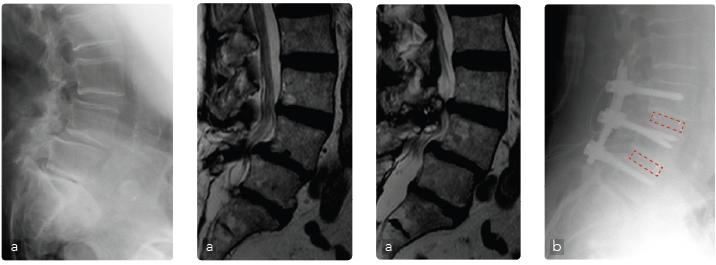

Caso 1: Spondilolistesi L4-L5 degenerativa

Maschio, 79 anni, spondilolistesi L4-L5 (cardiopatico 4 bypass). Operato 25 anni prima di discectomia L5-S1. Lombosciatalgia cronica aggravatasi negli ultimi 6 mesi e cluadicatio vertebrale con iniziale riduzione della forza. Il quadro radiografico e la risonanza mostrano una stenosi del canale a 2 livelli e la spondilolistesi L4-L5 (a). Operato di decompressione, riduzione dell’olistesi, artrodesi intersomatica e posterolaterale strumentata L3-L5 (b). Ottimo recupero funzionale a 4 mesi.